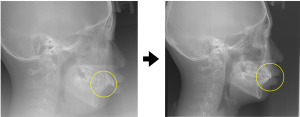

※治療後の頭部X線規格写真

治療後の頭部X線写真(上記)を見ると、黄色で囲った部分に示すように、上の前歯が前に出ていた状態が改善していることが確認できます。

※矯正治療前後の頭部X線規格写真の比較(上記写真左:術前、右:術後)

前歯の噛み合わせが改善している様子が確認できます。

前歯が前に出ている状態では、見た目の問題だけでなく、口を閉じにくくなることでお口の中が乾燥しやすくなり、さまざまなトラブルにつながることがあります。今回の症例では、前歯の位置を整えることで、見た目と機能の両面に配慮した治療を行うことができました。